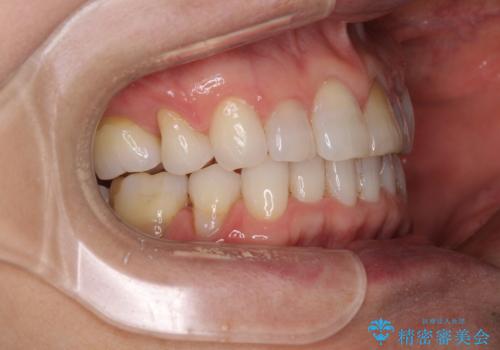

矯正治療の後戻り インビザライン・ライトでの再矯正

- 上下前歯を中心に、以前行った矯正治療の後戻りが気になるとのことで来院された患者様です。

後戻りは軽度であったため、インビザライン・ライトにて治療を行うこととしました。

矯正治療後は、再度後戻りすることを極力回避するために、下顎前歯の舌側を細いワイヤーを用いて保定することとしました。